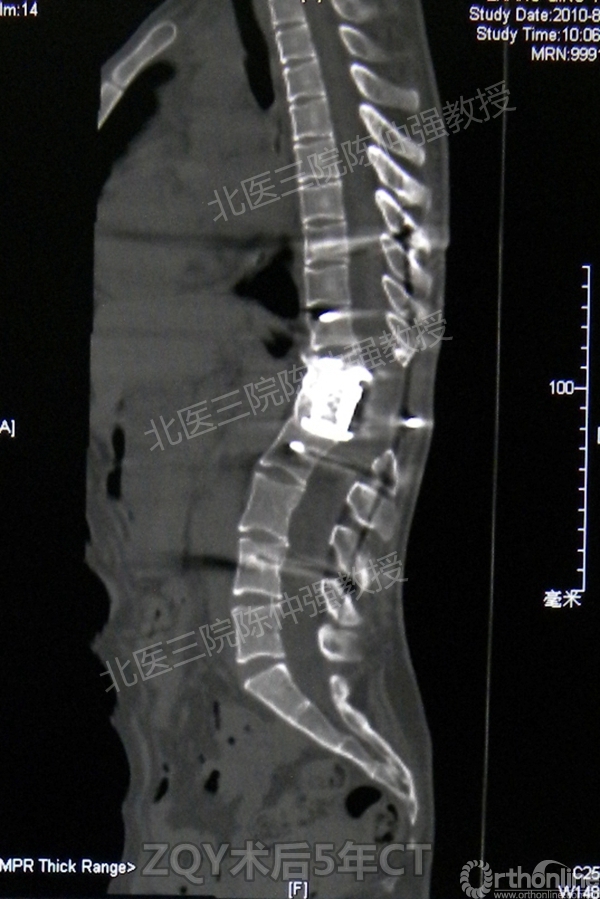

2005年,陈仲强教授在AOSpine年会上分享了一例胸腰椎陈旧结核性侧后凸畸形病例。资料如下:

ZQY术后5

患者女性17岁,胸腰椎陈旧结核性侧后凸畸形,局部呈“麻花状”扭转,无神经功能受损表现。2005年,陈仲强教授带领团队实施后路+侧前方联合入路脊柱节段切除、双轴旋转矫形术。术后患者外观显著改善,神经功能正常。术后随访证实患者截骨矫形节段骨性融合良好,矫形效果持续良好。